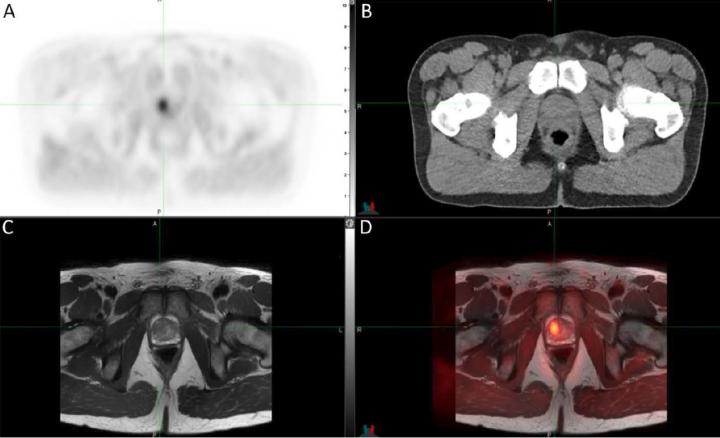

Prostate Cancer X Ray Images - Current Imaging Techniques For And Imaging Spectrum Of Prostate Cancer Recurrence And Metastasis A Pictorial Review Radiographics - The earlier the detection of prostate cancer, the better the patient’s chance of survival is.